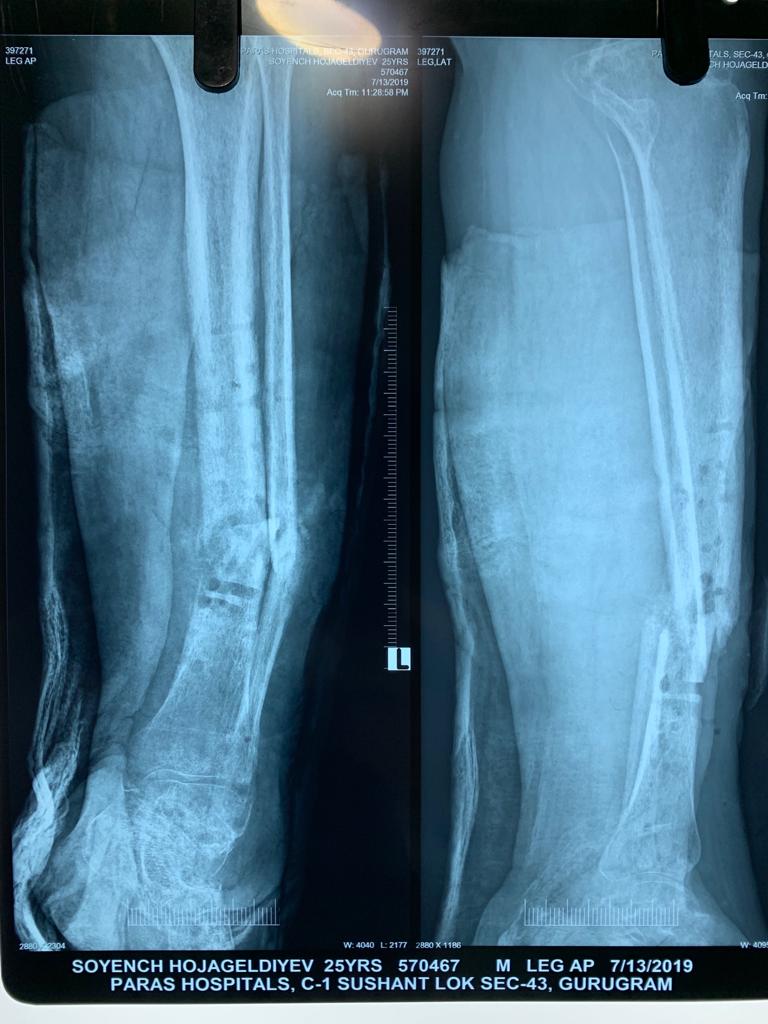

Another common scenario is one in which patient comes to us with open fracture of leg with an ununitied fracture with infection of bone and soft tissue previously elsewhere operated. In such cases the daunting task is to get rid of the infection and heal the fracture; here the technique of distraction osteogenesis (Ilizarov) comes to our rescue. First to get rid of the infection we get a pus culture done to assess the severity of infection and to assess the antibiotics that will be useful. During surgery we remove the dead and infected bone and soft tissues and bring the fracture ends together (docking), and apply the fixator (Monorail). Then we create a cut in the bone (corticotomy) and apply a distraction compression unit to help in creating a gap in the bone to allow distraction osteogenesis. Also antibiotic beads with the sensitive antibiotics are put at fracture site to kill the infection. Gradually over period of weeks the limb get lengthened to normal and infection is healed. The fracture also starts to heal by 3-4 months. The whole process might take upto 6 months.

Below are Xrays of one such case treated successfully by us over a period of 6 months.